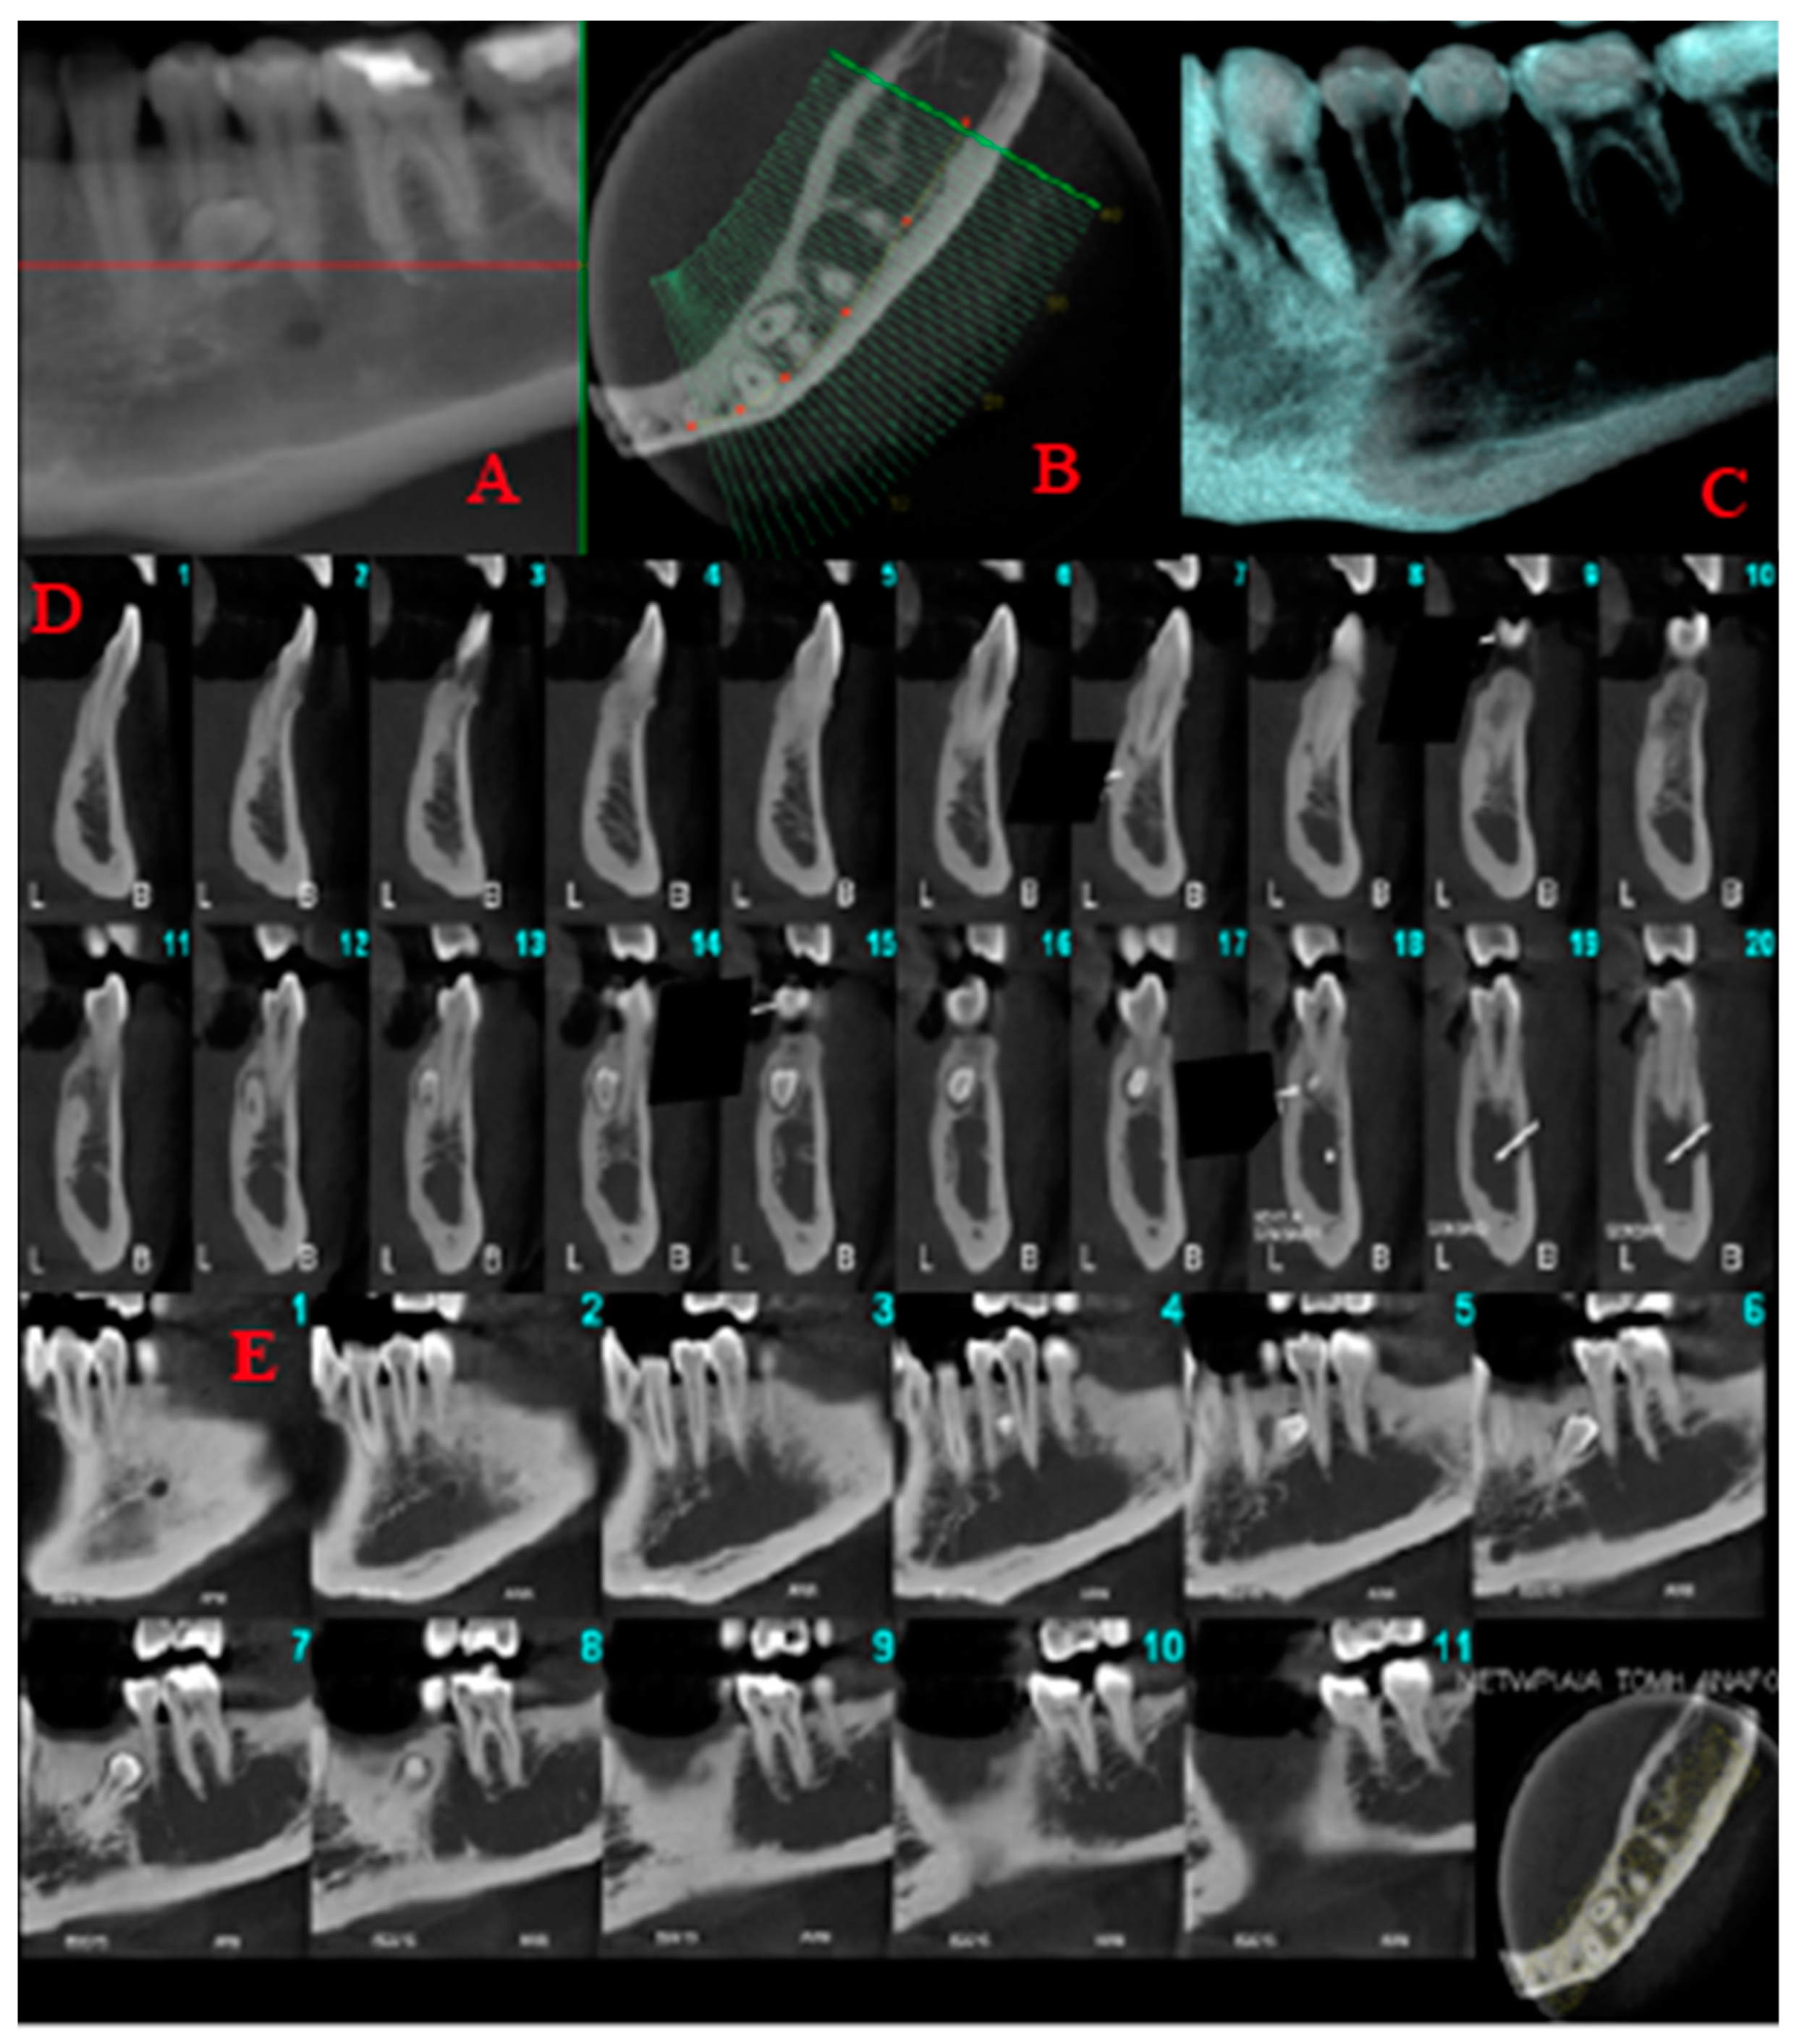

2.1. Case 1

Case 1 Presentation